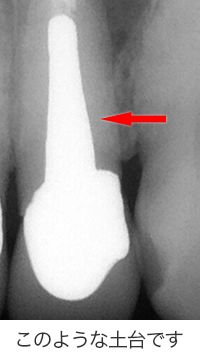

「この歯には、長くて太い金属の土台が入っていて、この金属の土台を取ろうとすると歯が割れてしまうので、治療ができません。なので抜歯です。」

確かに長くて太い金属の土台を除去するのは難しい治療と思います。

ほんの少しでも操作を間違えれば、歯を割ってしまったり歯の根に穴を開けてしまったりします。

地味ーに少しずつ少しずつ金属の土台を削って、少しでも心配ならレントゲンを撮ってと手間暇惜しまずかけて除去したのです。

大阪の根管治療の専門の先生がこの方法を発明しまして、以下の写真の様にマイナスドライバーを2本使ってテコの原理を用い金属の土台を除去します。